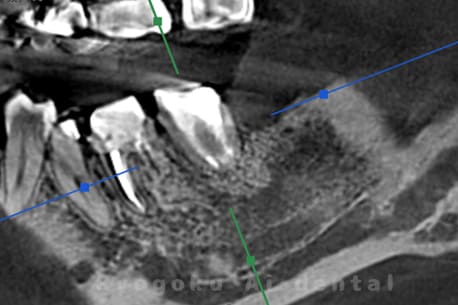

左下の違和感が消えず、数医院を周り、抜歯と判断され、治療を断られた患者様です。十分な説明の下、根管治療並びに歯周再生療法の話をし、同意を得て、行いました。術後経過も良好で、抜歯をせずに歯を残すことができました。

<リスク・副作用>

術後は痛み、腫れ、痺れなどの副作用が生じる場合があります。症状が再発する可能性があります。